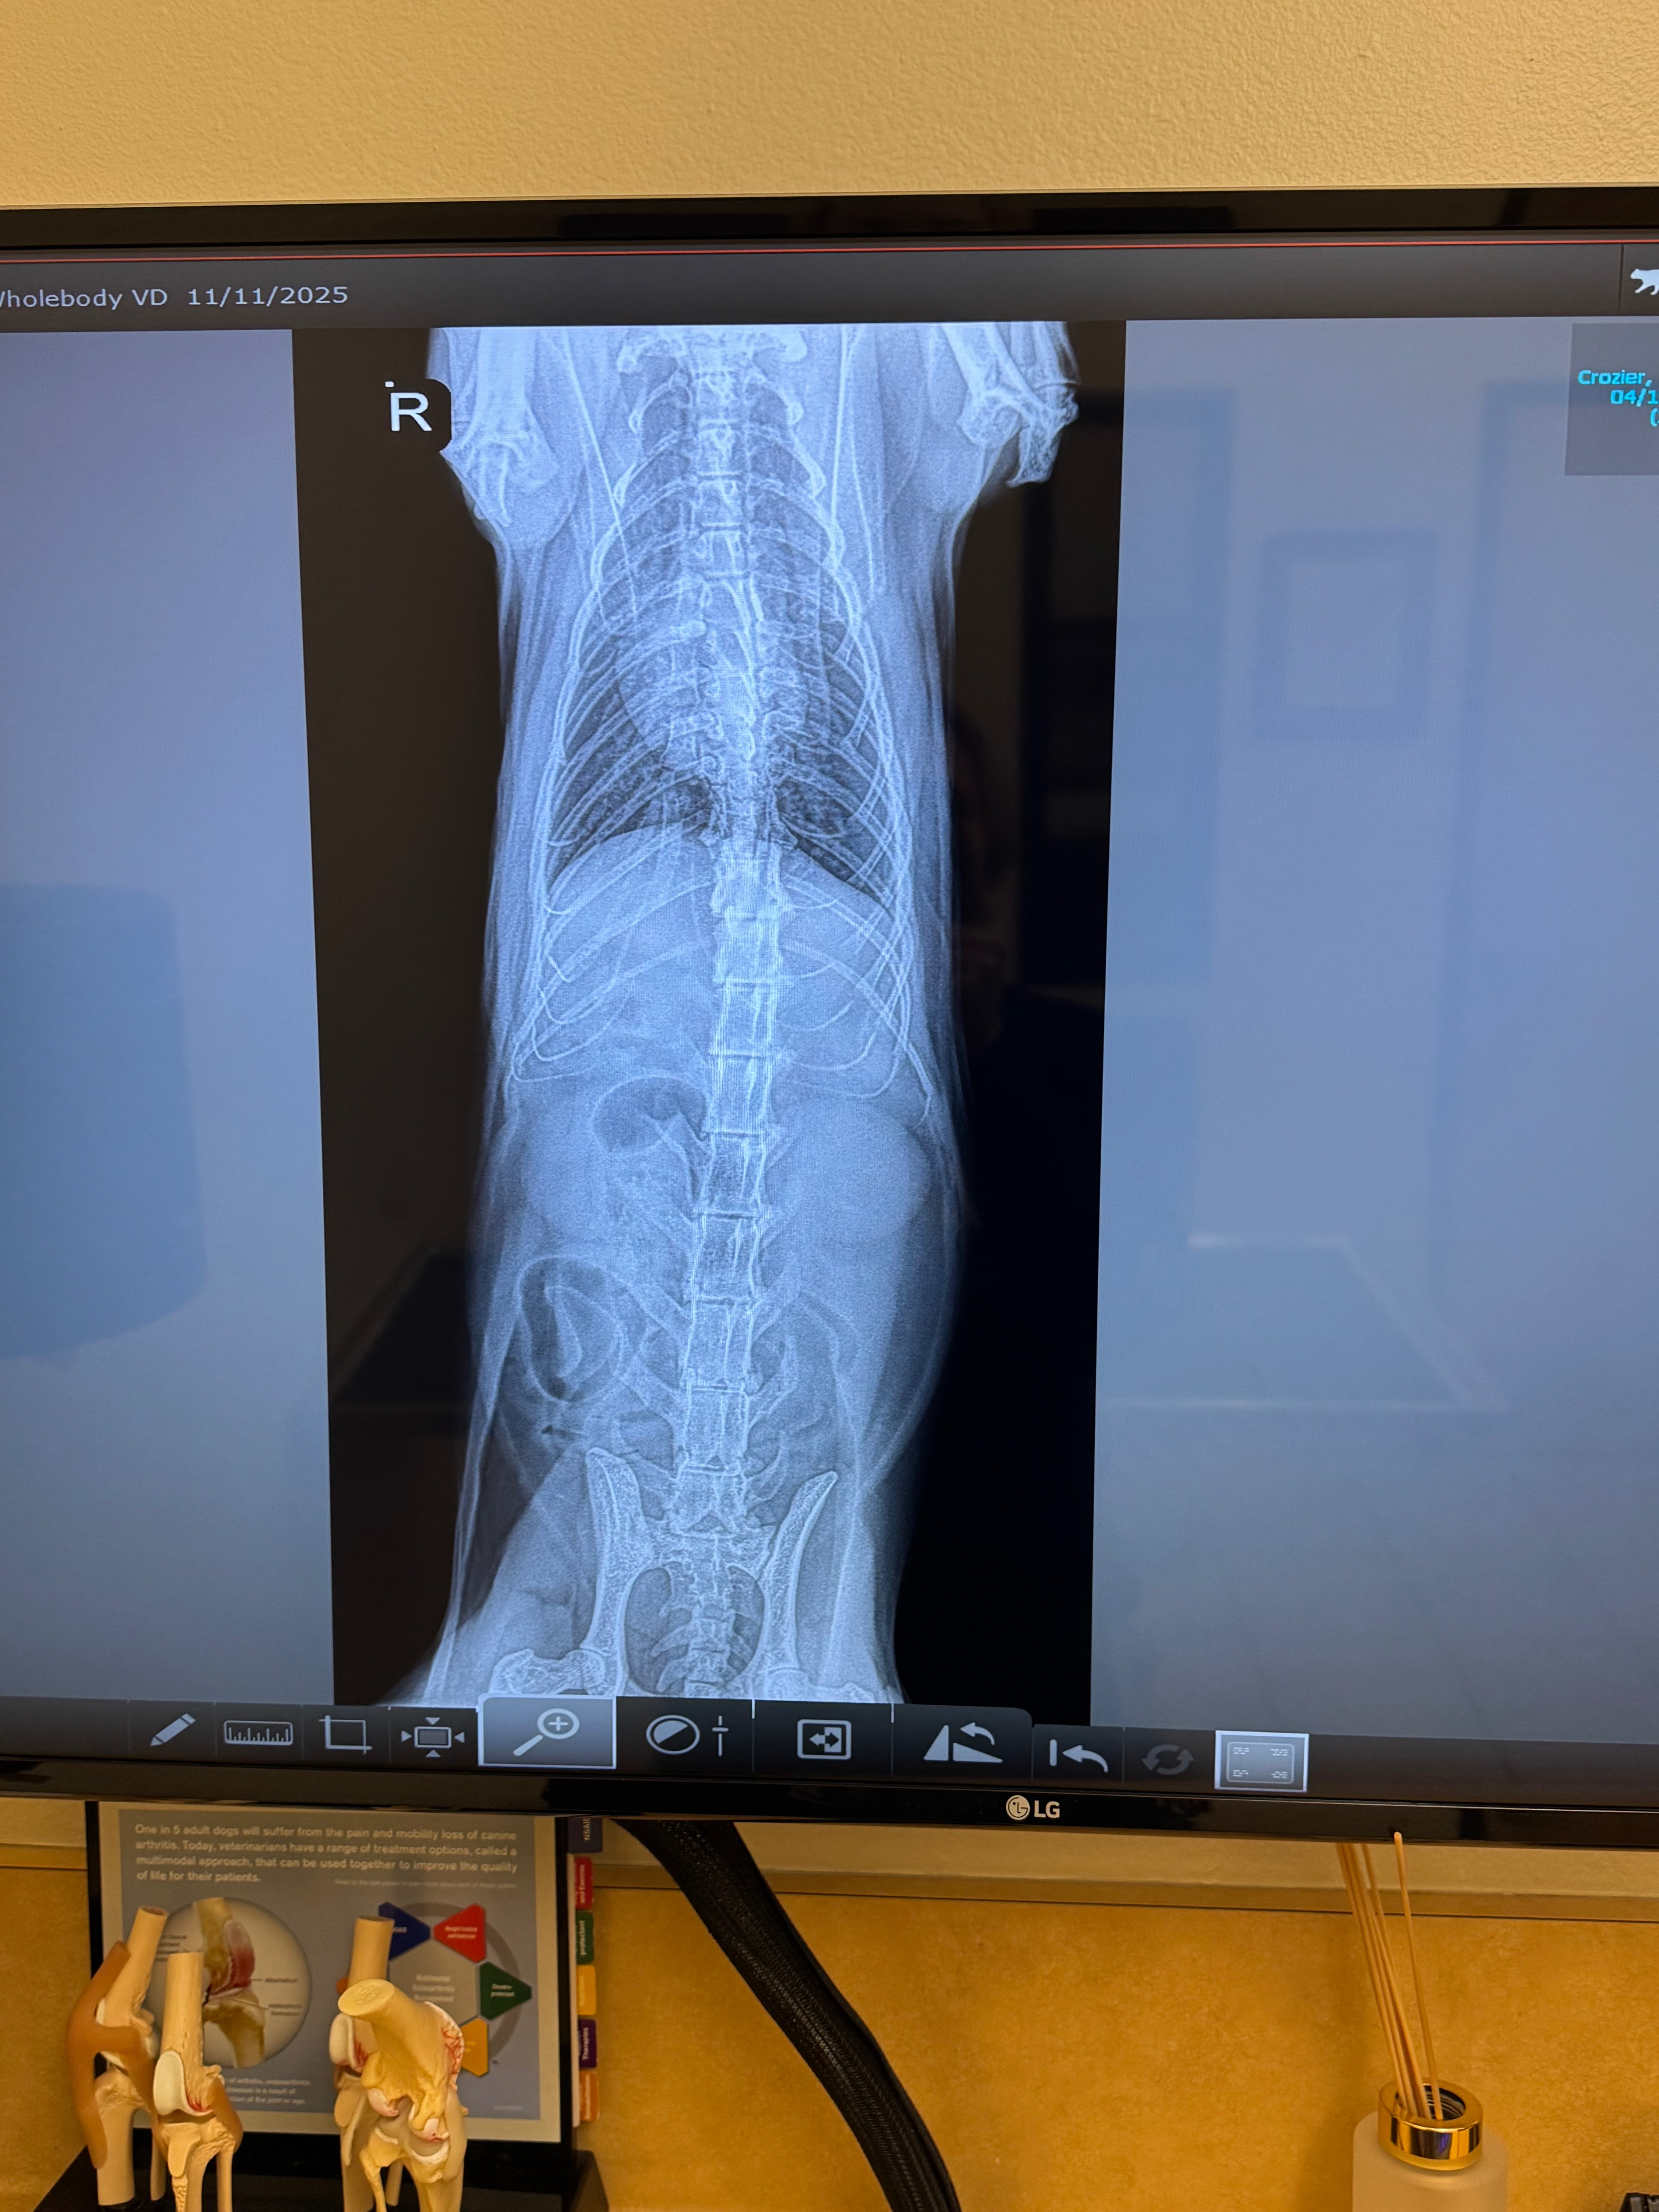

There’s not a whole lot at the moment we can do besides pain management and attempting to get him to eat and drink, but we need to get an ultrasound done on him to further treat what’s going on. The vets never figured out what was wrong with his sister, but luckily my kitty’s condition seems to be slowed with his current treatment. The X-rays show gas in what the doctors believe is his small intestines but it is unclear if it is being caused by blockage or inflammation (needs an ultrasound to confirm). I just had a major shoulder surgery in mid-September that I am still recovering from (physically and financially) and am going to school full time at CSUF. This cat has been by my side through sleepless school nights to road trips and sitting in my lap playing Skyrim/Stardew Valley on my Switch. He has been my home for the past 5 years and I can’t see him continue to live in pain.